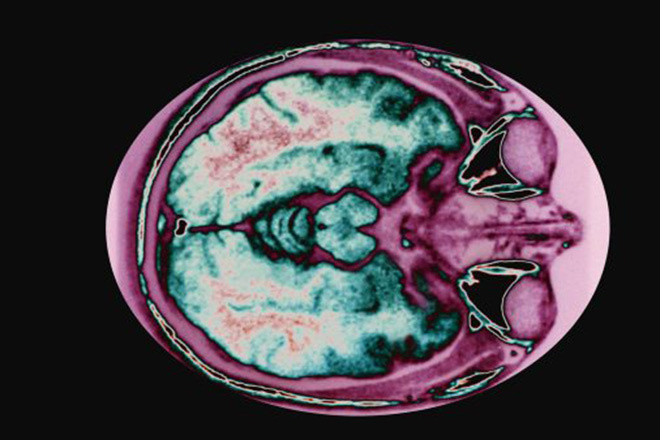

Фото: Custom Medical Stock Photo/Global Look Press

Американские исследователи разработали новые наночастицы, способные замедлить отёк и накопление жидкости внутри мозга при черепно-мозговых травмах. Результаты работы специалистов опубликованы в журнале Annals of Neurology.

Из-за кровоизлияний или черепно-мозговых травм массово гибнут клетки в отдельных областях головного мозга. Это приводит к ужасным последствиям для человека, от ухудшения работы сознания до потери речи, парализации или потери памяти. Сейчас единственным эффективным способом в борьбе с отёком мозга является трепанация черепа.

Кесслер с коллегами нашли способ замедлить развитие отёка. Их эксперименты показали, что он вызван набуханием нервных клеток. Они увеличиваются в размерах из-за того, что в мозг проникают иммунные тельца особого класса — гематогенные моноциты. Эти клетки расширяются, чтобы привлечь внимание других иммунных клеток. В других органах данный процесс ускоряет выздоровление, но при черепно-мозговых травмах часто приводит к смерти.

Исследователи пришли к выводу, что мигрирующие моноциты можно обмануть с помощью приманки, а именно полых наночастиц, покрытых антителами. При введении их в кровь, как показали тесты на мышах, иммунные клетки отреагируют на них и отправятся ликвидировать угрозу, игнорируя мозг. Это и уменьшает тяжесть отёка.